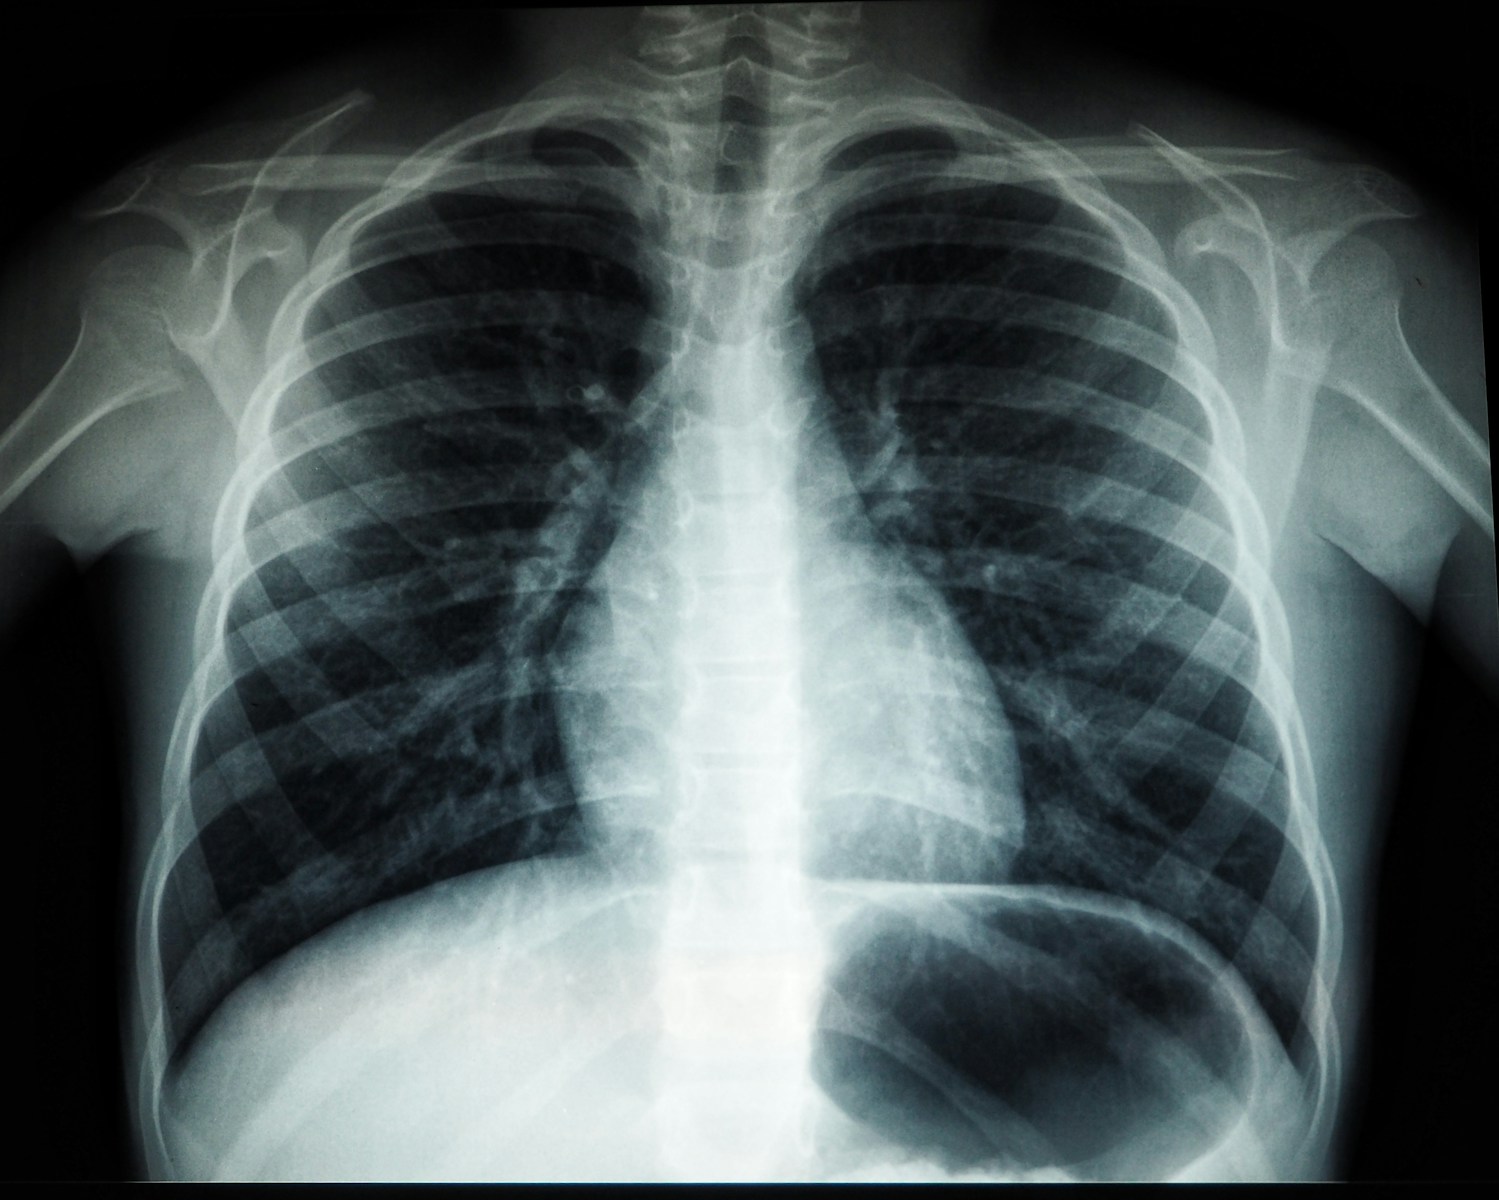

În cadrul activităților, fiecare persoană a completat chestionarul de screening și a semnat acordul informat. Persoanele care au efectuat investigația radiologică au fost informate despre riscurile tuberculozei, măsurile de prevenire, importanța depistării precoce, precum și despre posibilitățile de a efectua gratuit tratamentul.

În total, au fost examinate peste trei mii de persoane, dintre care 146 au fost identificate ca suspecte de tuberculoză. În urma investigațiilor suplimentare, au fost confirmate 27 de cazuri de TB, care au fost incluse în tratament. Rezultatele investigațiilor radiologice au fost comunicate sistematic instituțiilor de asistență medicală primară, iar persoanele suspecte sau cu alte patologii au fost luate la evidență și monitorizate de medicul de familie și medicul ftiziopneumolog.